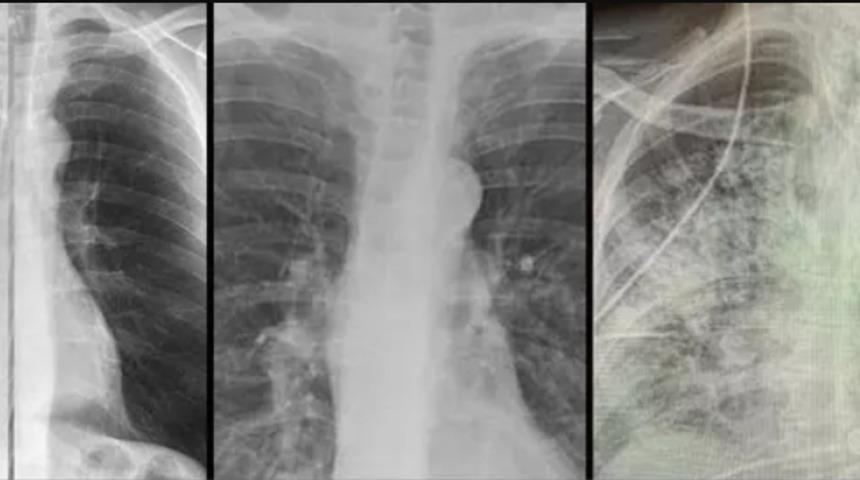

ABD'li bilim insanları koronavirüsün ciğerlere bıraktığı hasarı gözler önüne serdi. Sağlıklı, sigara içen ve Covid-19 hastası üç kişinin röntgen sonuçlarını yan yana sıralayan uzmanlar, "Covid-19'un yarattığı hasar çok yüksek seviyede" dedi.

Bilim insanının paylaştığı röntgen sonuçları dikkat çekti. Soldaki görselde sigara içen bir bireyin akciğer filmi görülürken sağda ise koronavirüsü yenmiş bir bireyinki yer alıyor. Akciğer filminde siyahlar ne kadar fazlaysa o kişinin ciğer kapasitesi ve sağlığı o kadar iyi anlamına gelir. Beyazlığın artması akciğerin kapasitesinin azaldığı anlamına gelir.

Röntgen sonuçlarında koronavirüsü geçirmiş ve sağlığına kavuşmuş kişilerin ciğerlerindeki hasarın sigara tiryakilerinden çok ama çok daha kötü olduğunu gösteren Bankhead-Kendall, “Sağlıklı bir bireyin röntgen sonucunda siyah alan büyük olur. Bu da o kişinin ciğerlerine alabileceği oksijen seviyesini gösterir. Sigara içenlerde hafif hareler yer alırken Covid-19 hastalarının ciğerleri ise bembeyazdır. Yani bu da koronavirüsü yenenlerde bile akciğer sorunları yaşanabildiğini gösteriyor” dedi.

Bankhead-Kendall, kıyaslama yapmak için sağlıklı bir bireyin akciğer filmini de paylaştı. Koronavirüsü yenen kişilerin nefes alma sorunu yaşayabileceğine dikkat çene Bankhead-Kendall, Twitter üzerinden, “Bunu kimin duyması gerek bilmiyorum fakat koronavirüsü geçirmiş bir kişinin akciğerleri, yıllarca sigara içmiş bir tiryakinin ciğerlerinden çok ama çok kötü. Bu insanlar bayılıyor, nefesleri kesiliyor ve benzeri birçok sorun yaşıyorlar” dedi.